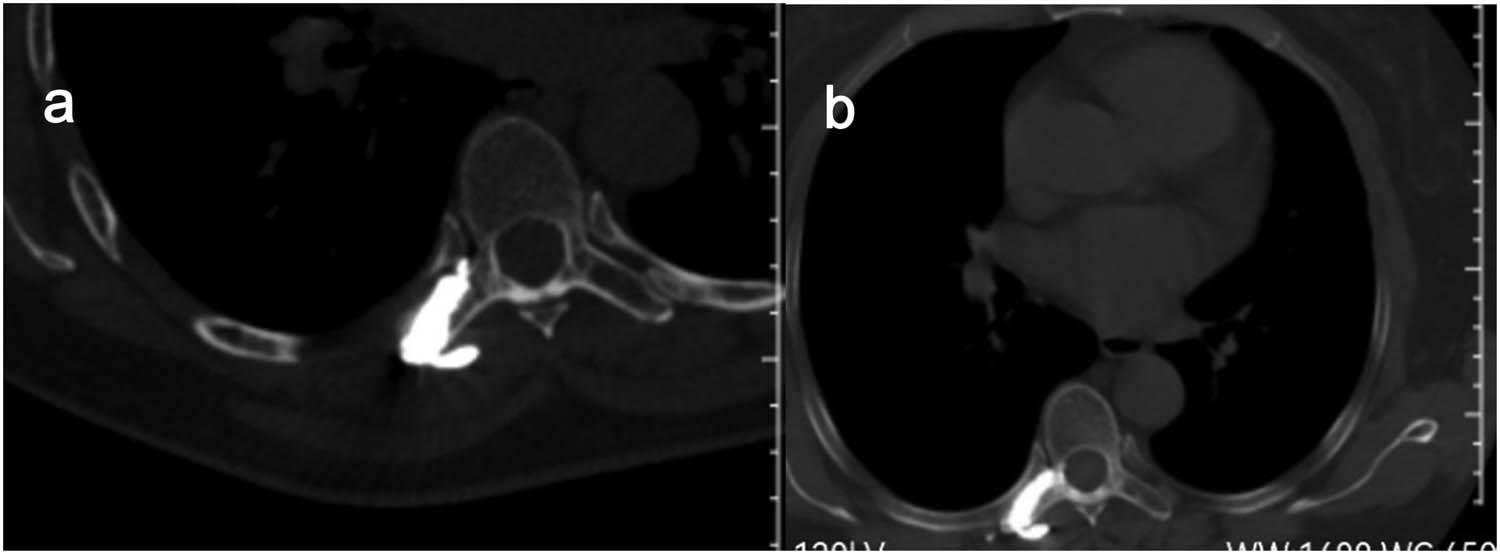

All procedures were performed using a Siemens Sensation 64 CT-scan (Siemens Healthcare, Erlangen, Germany) in the prone or supine position depending on the position of the lesion. The target lesion and needle path were located by non-enhanced helical CT acquisitions. Preoperative invasion range and destruction degree of adnexal tumor were determined and the injection route was planned according to X-ray, CT-scan, and MR (including enhanced) image data. After accurate marking of the skin and in strictly aseptic conditions, local subcutaneous injection of lidocaine 1% was performed at the defined skin entry point and an 11-gauge 15 cm co-axial needle (Dragon Crown Medical Co., LTD, China) was introduced step by step under CT-fluoroscopy (Figure 3a and b). After the needle was punctured into the right transverse process of T7 (adjusted during CT guidance), a 16G-gauge 20 cm MWA probe (ECO-100AL6, Nanjing Yigao Medical Technology Co., LTD, China) was advanced into the osseous lesions of T7’s right transverse process. Then connect the ablation needle to the ablation instrument (ECO-100A1, Nanjing Yigao Medical Technology Co., LTD, China), adjust the power to 70 W, and ablate twice for 2 min each time (Figure 4a). During the ablation process, the patient’s vital signs and the movement of the lower limbs were observed. After the ablation needle was withdrawn, the polymethylmethacrylate bone cement (PMMA, Heraeus Medical Ltd, German) was prepared in the appropriate ratio (powder (g)/liquid (mL) = 2:1) and was pushed with a cement-filled cannula (Dragon Crown Medical Co., LTD, China). The distribution of the bone cement is observed until it has diffused to the edge of the lesion (Figure 4b). After the bone cement has been filled, the cannulas were removed and the patient is returned to the ward for recovery.

On control CT scan performed during MWA (a) and bone cement was injected into the lesion during the operation (b).

After the procedure, the patient felt painless and the VAS score was 1/10. No complications occurred during the operation. CT showed that the cement was well filled and no leaks at the right transverse process of T7 (Figure 5a). At the 6-month follow-up, the patient’s chest and back pain was relieved, and a repeat CT revealed no leakage of bone cement and no new destruction of bone (Figure 5b).

Postoperative CT showed intact cement filling and no leakage in the spinal canal (a) and follow-up after 6 months showed no displacement of the bone cement and no new bone destruction (b).